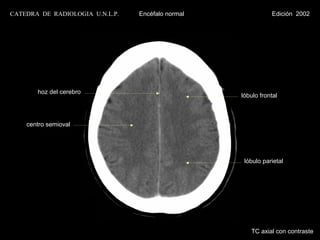

CATEDRA DE RADIOLOGIA U.N.L.P.   Encéfalo normal              Edición 2002

hoz del cerebro

lóbulo frontal

centro semioval

lóbulo parietal

TC axial con contraste